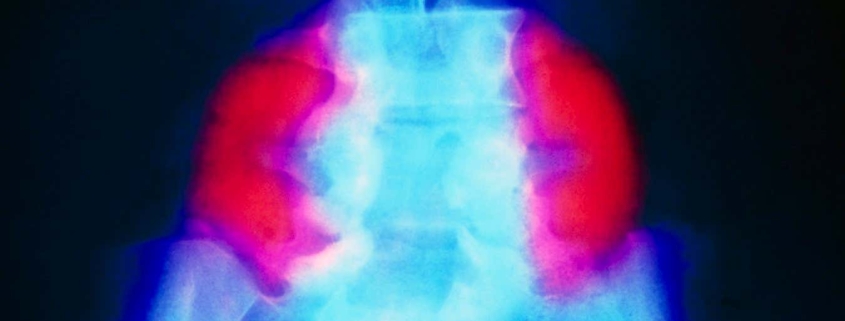

One of the most significant findings from the trial relates to a common complication called hindbrain herniation, which affected all six fetuses at the time of surgery. This condition occurs when excess fluid accumulates in the skull, forcing the cerebellum (the brain’s coordination center) to protrude through a hole at the base of the skull. While standard surgical intervention often helps reduce this herniation, many children still experience ongoing neurological complications.

The results from the stem cell patch trial are remarkable: MRI scans performed after birth showed complete reversal of hindbrain herniation in all six babies. Additionally, the surgical sites healed beautifully with no evidence of abnormal cell growth—a critical concern given the powerful regenerative properties of stem cells. “A key worry was that adding stem cells in a fetus would make the cells grow like crazy, but we didn’t see that,” notes Dr. Farmer.